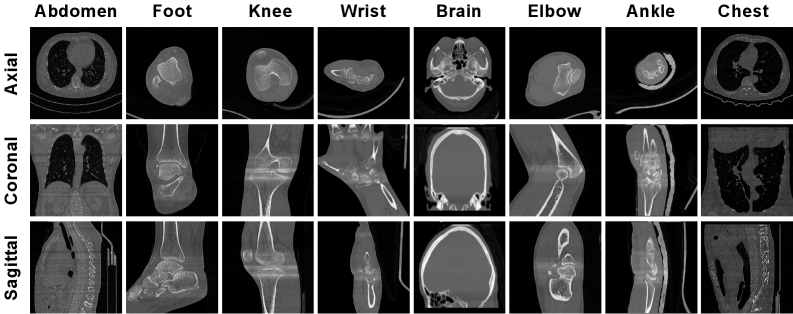

Figure 1. We present CT examples of different anatomical regions from our MORE dataset, with the three rows displaying visualization results in the axial, coronal, and sagittal planes, respectively.

Data Distribution Our dataset covers a wide range of anatomies and lesions, including Spine, Knee, Ankle, Wrist, Elbow, Foot, Patella, Gallbladder, Lung, Liver, Appendix, Brain, Kidney, Ureter, and Arachnoid Membrane for CT scans. We show the specific distribution in Figure 2 and some typical samples in Figure 1.